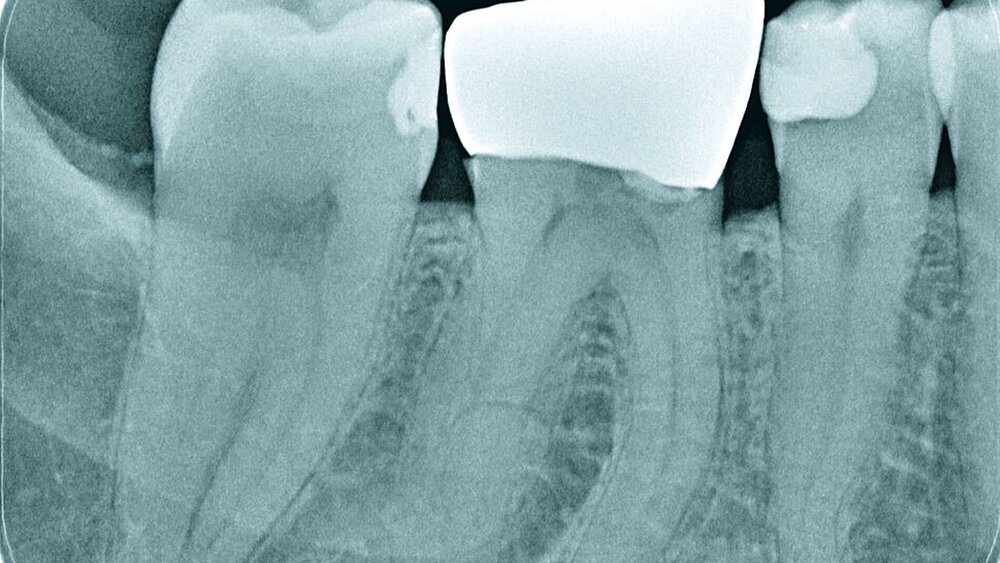

Röntgenbilder können genutzt werden, den anatomischen Schwierigkeitsgrad zu ermitteln. Lässt sich ein Wurzelkanal vollständig bis zum Apex mit einem Krümmungswinkel bis zu 30 Grad und einem großen gleichmäßigen Krümmungsradius erkennen, ist keine erhöhte Schwierigkeit in der Therapie zu erwarten (Abbildungen 1 und 2).